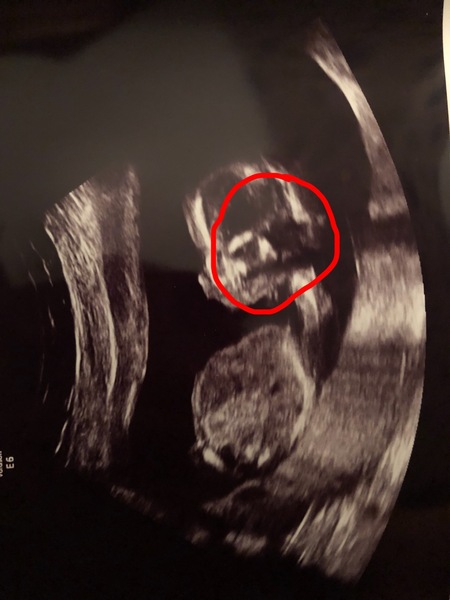

I had my scan tonight and i officially know what I’m having! Very excited.

A bit of a weird one though... the first thing my partner and I saw was a very creepy face on the baby’s head. I will post the photos with this.. please tell me that everyone else can see it too!?

What the hell is it 😩it’s so creepy

I’ve circled the face!

We are having another boy 😍 I thought I might be a little disappointed as I already have two and both my partner and I wouldn’t have minded a girl but I booed my eyes out with happiness. I love him so much already and the feeling of wanting a girl just disappeared πŸ’™πŸ’™

@7415N1d0r1391117 oh I see it now. How lovely I have a dd and I’m really not bothered but would quite like another girl.

@7415N1d0r1391117 it's when the baby looks straight at the ultrasound, we had it too!

@7415N1d0r1391117 are you being haunted by Bert from Sesame street?! I'm sure it's nothing, human brains just love to see faces in stuff.